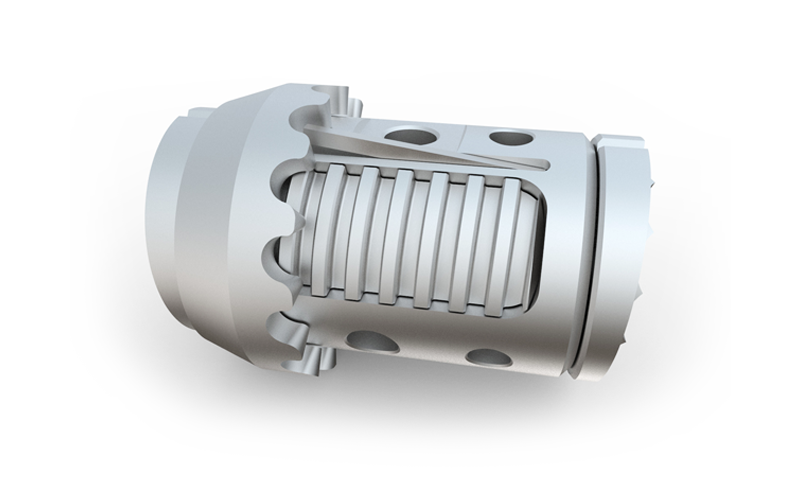

KINERA ist ein einzigartiges System auf dem Markt. Die Besonderheit liegt am Design des Schraubenkopfes. Medio-Lateral ist der Kopf schwenkbar. Kranio-Kaudal ist der Kopf fixiert. Durch den Einsatz einer Wippe im Schraubenkopf, welche sowohl den Stab von der unteren, als auch von der oberen Seite umschließt, wird die notwendige Flexibilität auch in Kranio-Kaudaler Ebene gewährleistet.